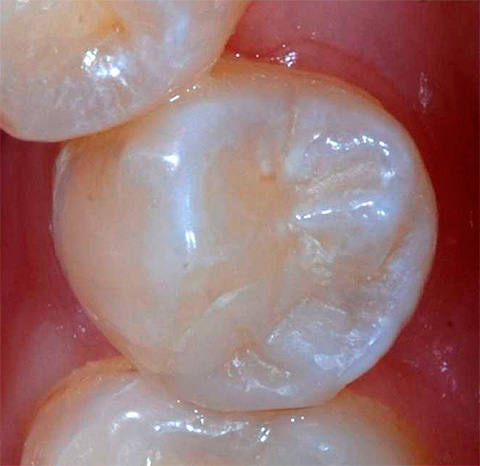

Esempi di lesioni cariose dei denti, loro perforazione e successivo riempimento

La carie dentale è accompagnata da una violazione dell'integrità del dente con la formazione di una cavità. Tuttavia, non pensare che un foro sarà necessariamente visibile nel tuo dente: spesso una cavità cariata non viene visualizzata e può essere trovata solo all'appuntamento del dentista quando si sonda un dente con uno strumento speciale per diagnosticare la carie.

Tuttavia, ci sono casi abbastanza comuni in cui il paziente stesso vede una formazione di cavità nel dente, poiché con la carie della dentina il quadro clinico è piuttosto ricco di sintomi associati. Questi includono: